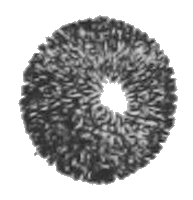

The annexed drawing exhibits the granules and animalcules of a human male being magnified from 900 to 1,000 times:—

1. Animalcules of a man, taken from the Vas Deferens, immediately after death.

2. Seminal Granules.

3. A bundle of Animalcules, as grouped together in the Testicle.

4. Seminal Globule.

5. Same surrounded by a cyst or bag.

View larger image